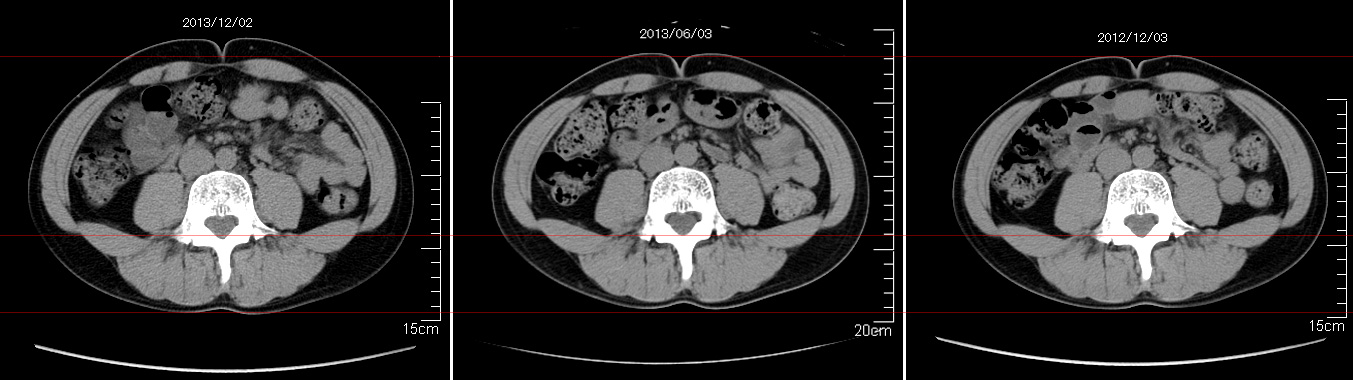

2006年入院治療の退院日から10年。 かなり大きな節目なんだが、なんだろうこの軽い感じは(笑)。 「10年生きたんだぁ」くらい。 変わったような変わっていないような。 当時は10年後なんて全く考えていなかった。 今も10年後は考えていないが・・・。 退院前日の2006/10/31は46.6kgだった。 今日計ったら54.8kg。体脂肪は16.6%。 とても健康にストレスなく生活できていることに、治療当時から現在に至るまで、関わった人全員に感謝の気持ちです。 マーカー、CT画像、問題なし!! 血液検査結果もほとんど文句なしの正常値。 そうだなぁ、数値に出ない異変としては、肩凝りかなぁ。 一旦夏になくなったと思ったが、初秋から再発。 マウスを左手にしたり、シップ貼ったり、最近はホッカイロ貼ったり。 で、一向に良くなる気配がない。 やはり四十肩なのか。 でも肩の可動域は問題ない。動かせないような痛みも無い。 結局色々考えてたどり着いたのは「変形性頚椎症」ではないかと。 肩凝りや頭痛がダラダラと続くようになるという症状がピッタリ当てはまる。 さて、改善策がなかなか難しい。 整形外科行ってもレントゲン撮って湿布をくれるだけだろう。 そんなことに大金を出すならまずは300円/回のプールで泳ごうと思う。 重力から開放して全身運動をするのが一番良いらしい。 2015年の目標は少しでも良いから水泳を再開する、だな。 マーカー、CT画像、問題なし!! 通常の血液検査結果も文句なしの正常値がズラ~っと並んだ!! 間違いなくヨメの食事のおかげである。ほんとうに感謝である!! ちなみに最近少々腰周りの肉付きが気になっていたのだが・・・。 左から2013年12月、2013年06月、2012年12月と背骨の位置は合わせて並べてみた。 6月まではあまり変化がなかったが、この半年で明らかに違う。 背中側の脂肪がやや増えてはいる。 でも最も大きな違いは、腸なのか、やたらと内臓が膨れている・・・。 一言で言うと食べすぎ?!?! 食事は野菜中心ではあるが、確かによく食べているw。 せっかくスーツのウエストを詰めたんだからこれ以上にならないようにしたい。 「腹八分目を心がける」かな。